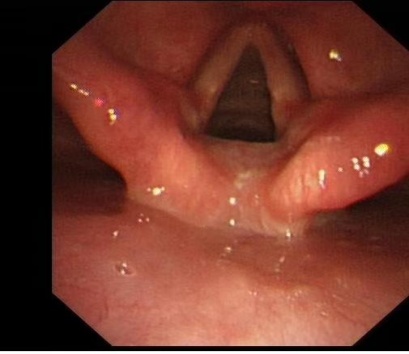

病例一:患者陈新,男,35岁,工人,因“发现肺部阴影1.5月,气短加重10天”入院。患者4天前体检发现肺部阴影,肺CT提示双肺纹理增多、紊乱,双肺多发片状模糊影,考虑感染性病变。患者自述活动后胸闷、气短,休息可缓解,曾规律口服醋酸泼尼松片(剂量递减),但已自行停药1周。入院后复查肺部CT显示右肺下叶实性结节(最大截面约19 mm × 13 mm,边缘毛糙),双肺间质性炎症。支气管镜检见气管及支气管黏膜光滑,管腔通畅,但右中叶内侧段可见白色粘稠分泌物,肺泡灌洗液送检。镜下可见肺泡腔内充满粉染、颗粒状蛋白性物质,其内可见泡沫细胞。

入院评估与初步检查:① 入院后完善肺CT检查,结果显示双肺纹理增多、紊乱,双肺多发片状模糊影,提示感染性病变;复查CT发现右肺下叶实性结节双肺间质性炎症。② 行支气管镜检查:观察气管及支气管黏膜光滑,管腔通畅,但右中叶内侧段可见白色粘稠分泌物,于右中叶内侧段行肺泡灌洗,使用生理盐水100 ml,回收65 ml灌洗液,留样送检。③ 病理诊断与特殊染色:标本经病理检查镜下可见肺泡腔内充满粉染、颗粒状蛋白性物质,其内可见泡沫细胞。④ 肺泡灌洗液标本特殊染色结果:AB-PAS (爱先蓝–糖原)染色及PAS (糖原)染色均呈阳性,提示肺泡腔内沉积物为蛋白性物质。⑤ 结合临床及影像学表现,诊断为肺泡蛋白沉积症(PAP)。最终结合临床考虑肺泡蛋白沉积症(PAP)。